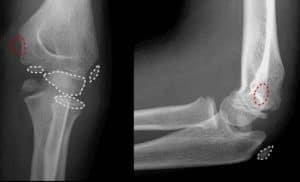

שבר במרפק יכול להיגרם באולקרנון (הקצה המחודד של המרפק), בראש הרדיוס (האמה) ובעצם הזרוע (שבין המרפק והכתף). הסעיף הרלבנטי בתקנות הנכות הוא סעיף 41 והוא מבחין בין שני מצבים:

גם שינוי בזוויות או הוצאת ראש הרדיוס, ללא הגבלה בתנועות יקנו 10% נכות.

שבר באולקרנון

שבר באולקרנון, נפוץ כי מיקומו הבולט מהגוף הופך אותו לפגיע בטראומה ישירה. הוא אינו מכוסה או מוגן על ידי שרירים. כאשר השבר עם תזוזה, מנתחים לשם קיבוע פנימי (ORIF). עם מתכת, ברגים, וסיכות קירשנר. לא מקבעים בגבס, מכיוון ששריר הזרוע האחורי עוקר את העצם ממקומה.

האולקרנון פגיע במיוחד בקרב ילדים. על פי האגודה האמריקאית לאורטופדיה, 10% מכל שברי העצמות הפוגעים בילדים הם שברים במרפק.